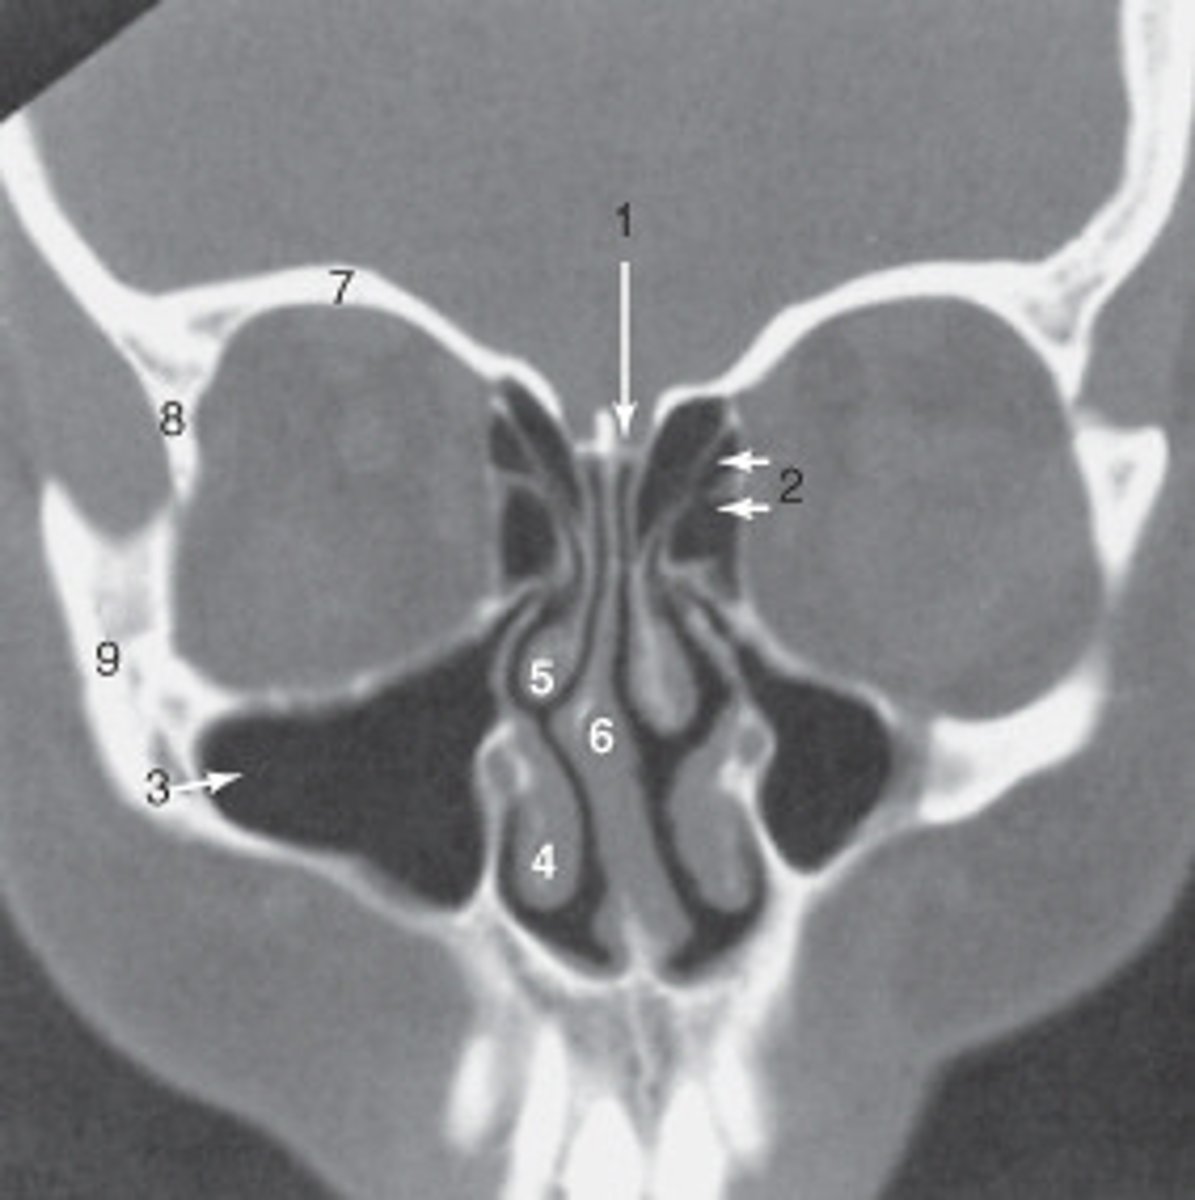

the nasal septum is labeled:

<p>the nasal septum is labeled:</p>

the ethmoid sinuses are labeled:

<p>the ethmoid sinuses are labeled:</p>

the zygoma is labeled:

<p>the zygoma is labeled:</p>

the lateral orbital wall is labeled:

<p>the lateral orbital wall is labeled:</p>

the structure labeled 3 is the:

<p>the structure labeled 3 is the:</p>

the structure labeled 7 is the:

<p>the structure labeled 7 is the:</p>